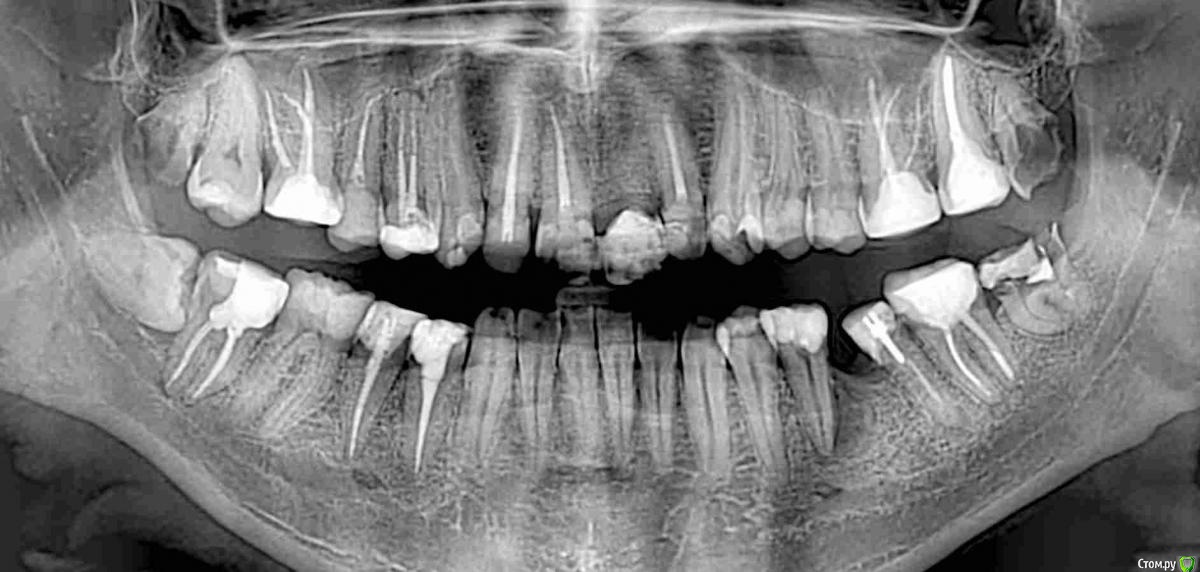

Trigger Опубликовано 28 января, 2020 Поделиться Опубликовано 28 января, 2020 Добрый день. Подскажите, что лучше поставить на место 36 зуба и почему. Пояснения:36 гемесекция была 10 лет назад в связи с невозможность перелечить корень. 1,5 года назад удалили второй корень, тк но сильно наклонен.35 возле корня было воспаление (видно на старом снимке) его убирали. Ссылка на комментарий

Trigger Опубликовано 28 января, 2020 Автор Поделиться Опубликовано 28 января, 2020 (изменено) Верх покрыл коронками, нижние (37, 35, 44, 45, 47) по плану. За все время лечения врач говорил только об импланте. Сразу не ставили, тк было воспаление у 35.Сделал свежее КТ. Все обговорили, что большая впалость десны, потребуется костная и десневая пластика и установка импланта. Мне оставалось только выбрать системы с которой врачи работают Astra tech или Dentium. Почитал, особой разницы не увидел. Везде вывод один, зависит от качества установки, а не фирмы. Переплачивать 10к смысла не вижу. Саму операцию врач передал коллеге. Он посмотрел, сказал, что идеально сделать не сможет и между импланом и зубами 35 и 37 останутся треугольные пустоты. Срок жизни 35, 37 после покрытия коронками оставляет 5-15 лет (тут у меня большие вопросы. Что у 35 было воспаление, может повториться и сколько ему останется это понимаю. но 37 пломбе более 10 лет меня не беспокоит) придется на этом участке ставить три импланта подряд.Предложил сейчас с костью, десной ничего не делать. Поставить мост 35-37. Когда с зубами что то случится сделать 2 импланта 35, 37 и тот же мост.Когда мне это все озвучили было очень неожиданно, тк вариант с мостом ранее не рассматривался вообще. Взял паузу на подумать.Пока склоняюсь к варианту ставить имплант. Мост даст бОльшую нагрузку на 35 и 37. Изменено 28 января, 2020 пользователем Trigger Ссылка на комментарий